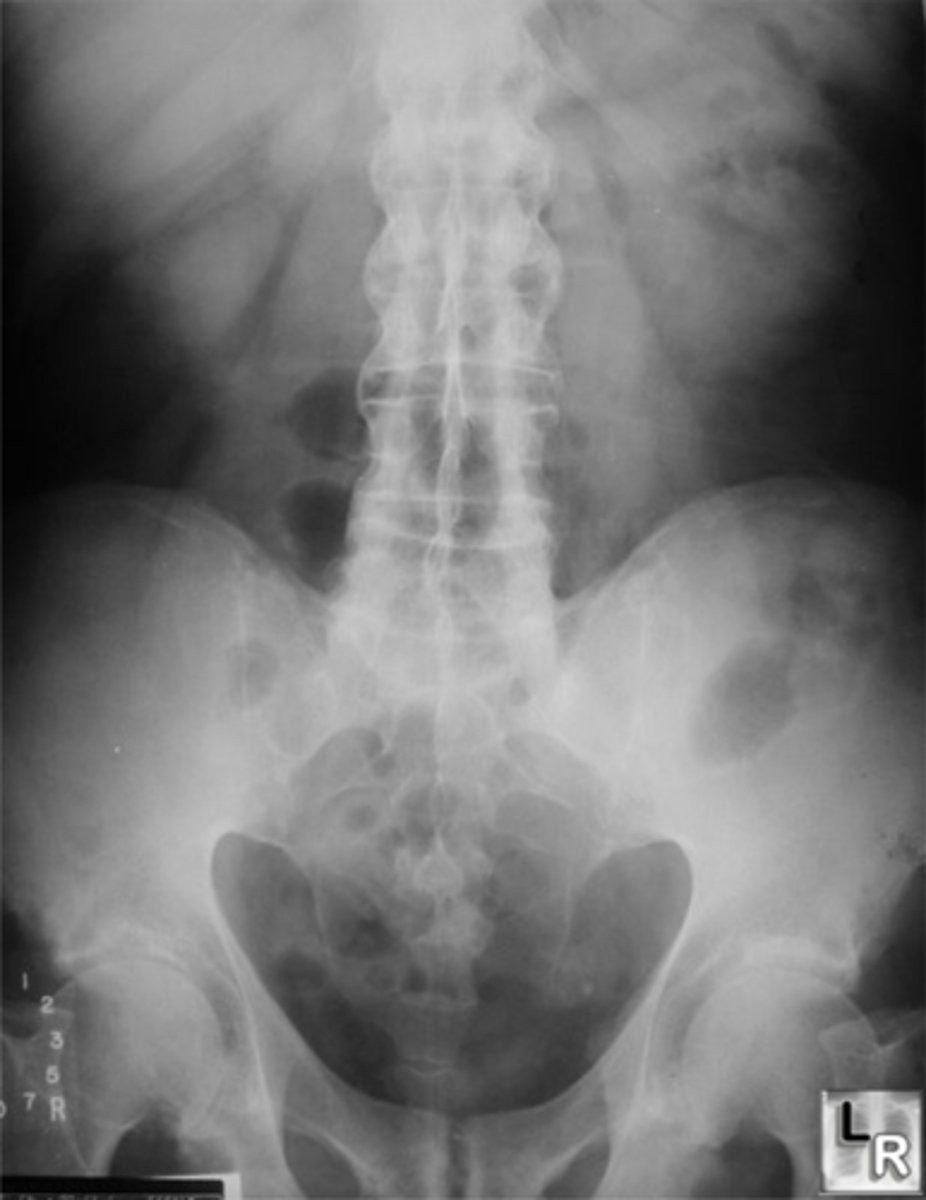

Vignette #1:

Sex: Male

Age: 62

Chief Complaint: Patient presents with low back pain and initiating urinary streams. He reports polyuria in the middle of the night.

Objective Findings: Kemps + Diagnostic Imaging: X-ray